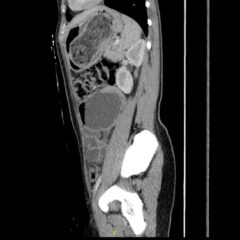

Sinonasal carcinoma is a rare malignancy that often presents with nonspecific symptoms, making early diagnosis challenging. Delayed recognition can lead to disease progression and worse outcomes. This case report emphasizes the importance of early identification, prompt imaging, and multidisciplinary management. A 73-year-old male with a history of anemia and hypertension presented with progressive facial swelling, 20-pound weight loss, and vision loss in the left eye over two months. Initially misdiagnosed with bacterial sinusitis, his symptoms persisted. Examination revealed a proptotic left eye and a large obstructive nasal mass. Computed tomography (CT) and MRI (magnetic resonance imaging) demonstrated a destructive sinonasal mass with skull base and intracranial extension. A biopsy confirmed sinonasal carcinoma, and the patient was started on chemoradiation therapy due to the inoperability of the tumor.

This case underscores the importance of recognizing red flag symptoms such as persistent facial swelling and neurological deficits. Multimodal imaging played a critical role in diagnosis. The literature suggests sinonasal carcinoma is often diagnosed late, reinforcing the need for early suspicion and specialist referral. Sinonasal carcinoma should be considered in patients with persistent facial or nasal symptoms. Timely imaging, biopsy, and interdisciplinary care are essential for optimizing outcomes.